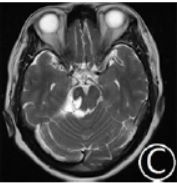

入院后头颅MRI平扫+磁共振断层血管成像检查,显示右侧三叉神经根部有一个囊性病灶,明显侵蚀脑干,T1像呈低信号,T2像呈高信号,无明显增强(图1)。

图1蛛网膜囊肿致典型三叉神经痛

MRI表现。A.冠状位T1像增强示病灶位于右侧桥小脑角区,呈低信号,无明显强化;B、C.轴位T2像示囊肿呈脑脊液信号,位于三叉神经根部,明显压迫桥脑上部和中脑